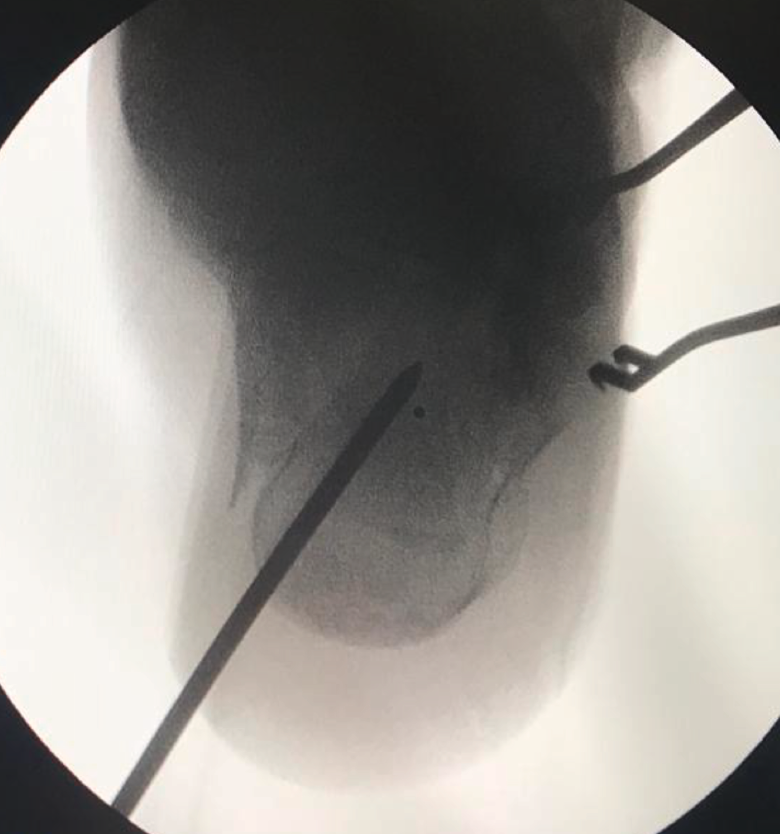

Figura 4. Proyección axial del calcáneo. Steinmann en la tuberosidad posterior para corregir el varo-valgo.

A la hora de corregir el varo-valgo y la longitud del calcáneo colocamos un pin Steinmann o aK de 3,0 o 4,0 en la tuberosidad posterior y damos angulación varo o valgo (Figura 4) según necesite cada caso y siempre comprobando con la fluoroscopia (proyección axial). Una vez conseguida la angulación correcta, se fija de forma definitiva con 2 tornillos canulados de posterior a anterior (Figuras 5 y 6).